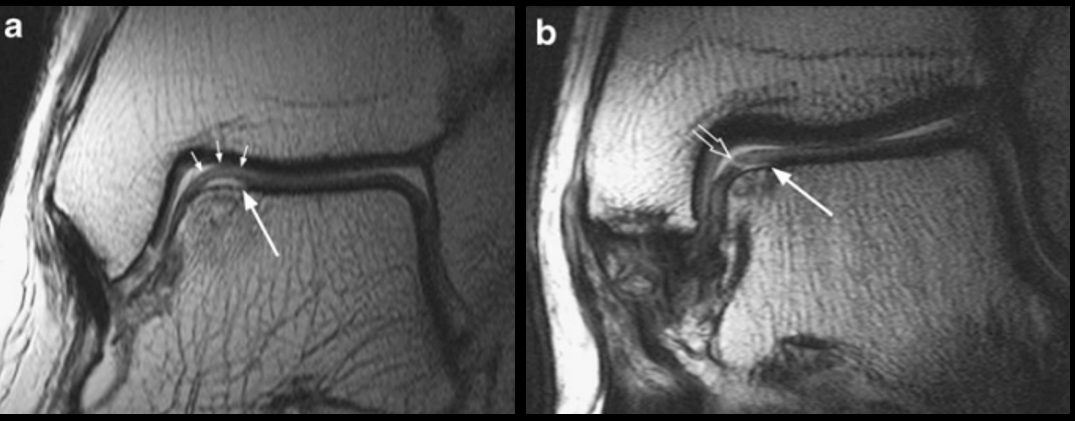

Рис. 6. МРТ: стадии 3а и 3б — отделённый, но не смещённый фрагмент

Рис. 7. МРТ: стадии 4а и 4б — смещённый остеохондральный фрагмент